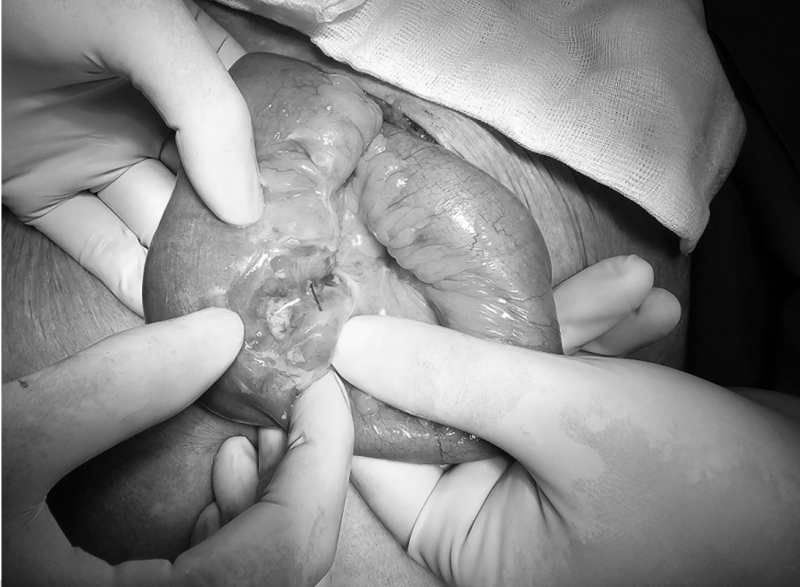

Tim bedah dipimpin oleh Dr. Duong Xuan Hiep, Kepala Departemen Bedah Umum. Selama operasi, para dokter menemukan benda asing, tulang ikan, yang telah menusuk usus halus.

Tulang ikan dikeluarkan dari perut wanita berusia 83 tahun